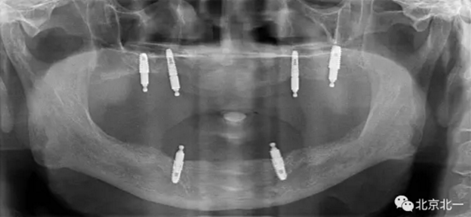

圖三:植體負(fù)重一年后脫落掉入上頜竇,

3.png